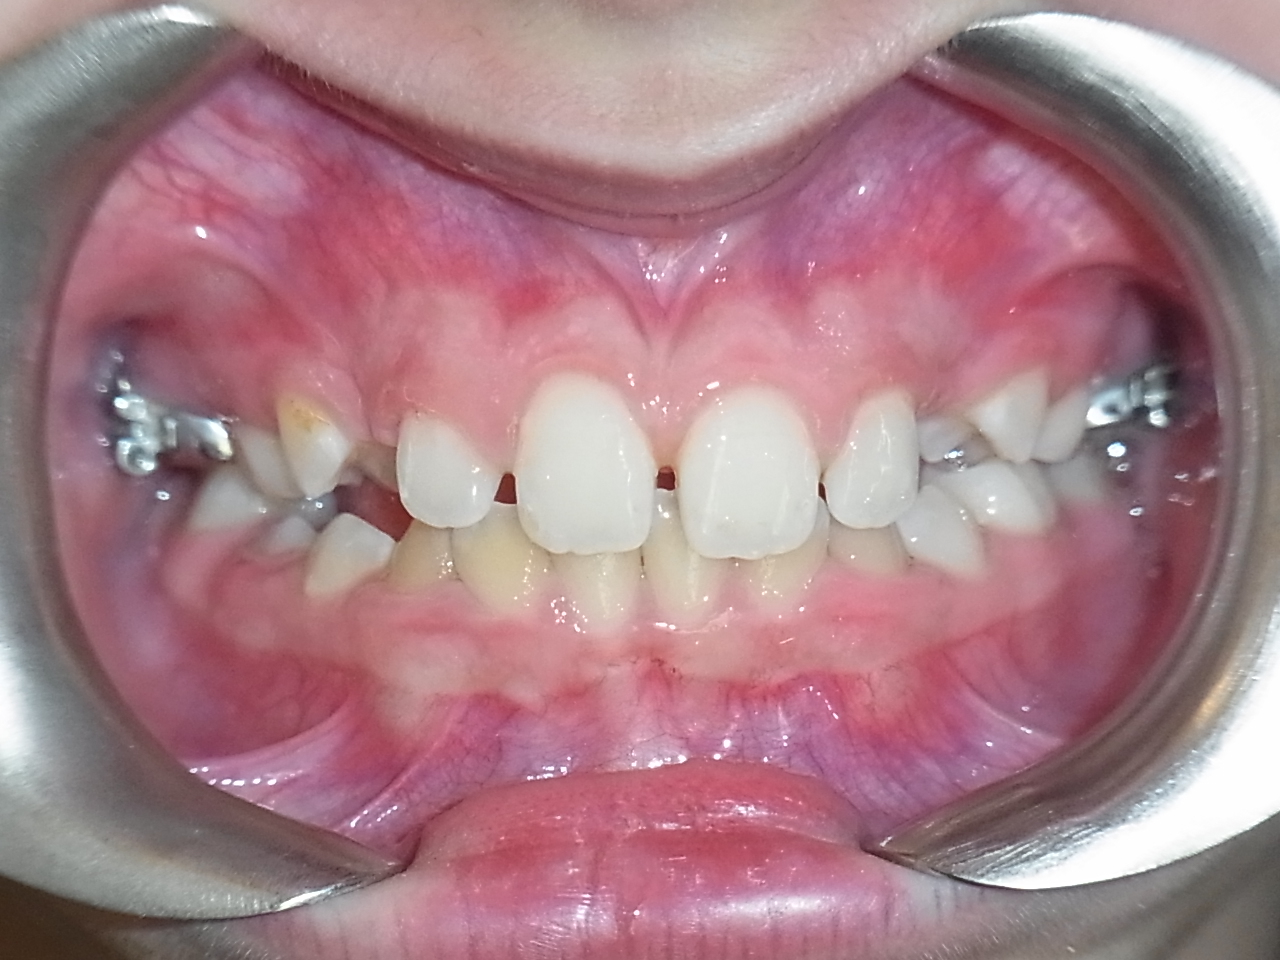

Visuels de droite : enfant de 10 ans présentant une béance des incisives.

Traitement par arrêt du pouce et rééducation linguale. Port d’un appareil Quad Helix.